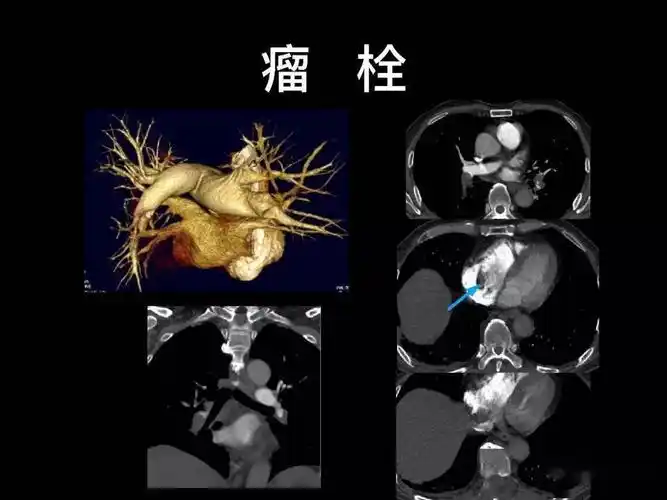

肺栓塞

图片示:左下肺动脉栓塞